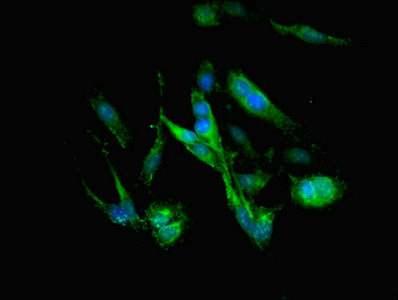

Immunofluorescent analysis of Hela cells using CSB-PA10599A0Rb at dilution of 1:100 and Alexa Fluor 488-congugated AffiniPure Goat Anti-Rabbit IgG(H+L)